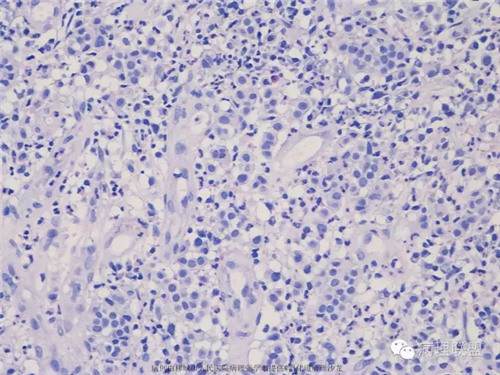

57岁,便血,距肛门5-9cm,梭形肿物5*3*3cm,根部宽1.5cm。

第二例病例解读

基本上是炎性肉芽组织,炎症重,中间夹着一些大小较一致似有排列的细胞,建议组化鉴别NET、浆细胞。